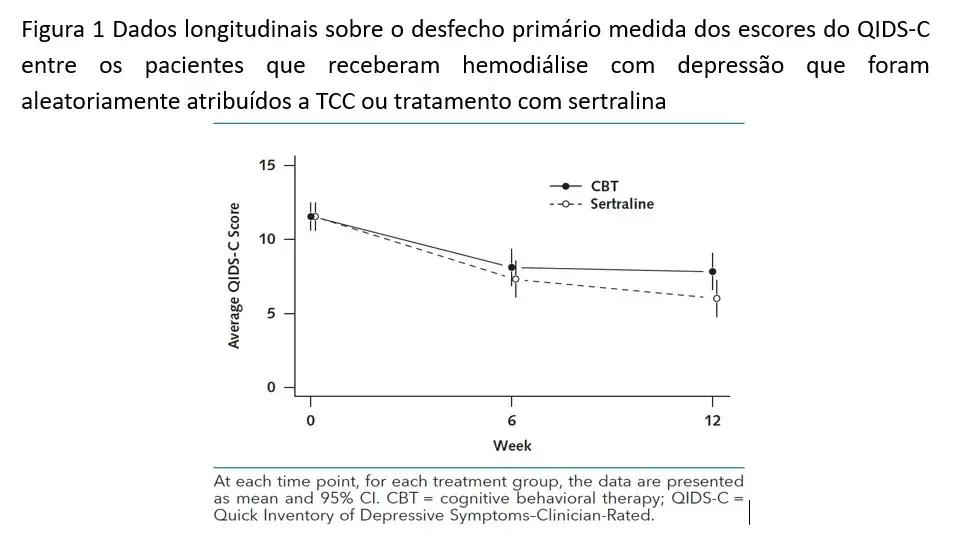

**Fase 2:** o desfecho primário foi a avaliação de 16 itens do Inventário Rápido de Sintomas Depressivos–Clínico- Escore classificado (QIDS-C) em 12 semanas. As pontuações foram avaliadas no início do estudo e em 6 e 12 semanas. Os pesquisadores eram cegos para a atribuição do tratamento e avaliaram o score por entrevista telefônica.

Já na fase 2, os escores do QIDS-C diminuíram entre os participantes alocados para o TCC (pontuação antes: 12.2; após 12 semanas: 8.1), bem como aqueles no grupo sertralina (pontuação antes: 10,9; 12 semanas, 5,9). As pontuações de depressão em 12 semanas foram **menores** no grupo sertralina do que no grupo TCC (estimativa de efeito da sertralina vs. TCC: QIDS-C, 1.84; P = 0,035).

- Os sintomas depressivos e vários outros resultados relatados pelos pacientes melhoraram tanto com a TCC quanto com a terapia com sertralina, mas as pontuações dos resultados em 12 semanas foram modestamente melhores para o grupo da sertralina.